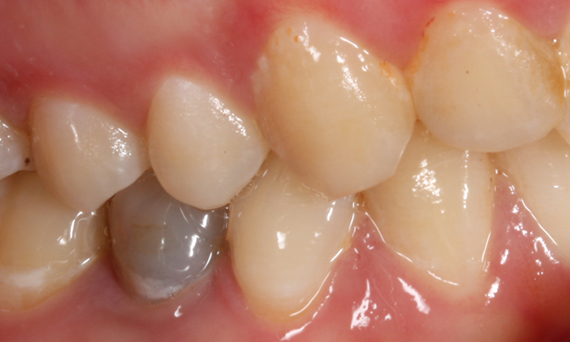

First upper molar, in 90 minutes

Katana Zirconia STML single crown

CEREC Primemill not only brings speed to the appointment, but also versatility in milling strategies. In this case we chose the Extra Fine milling mode to achieve maximum aesthetics and attention to details as possible.

Before: Fractured metal-ceramic crown on tooth 14, which had previously been treated endodontically.

After: Translucent full zirconia crown for an aesthetic result with maximum resistance and retention shape.